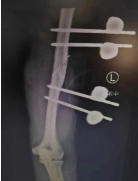

通过X光片检查显示李大哥左上臂为“肱骨开放性骨折、左尺桡骨骨折”,郑大伟主任迅速组织科室展开讨论,为其制定个性化手术方案。

随后,郑大伟主任、李刚、刘绍利医生手术团队对患者行“左上臂清创骨折复位外固定血管神经肌肉撕脱皮肤修复术”,手术紧张有序地进行,首先对撕裂的伤口皮肤进行修整清创后探查发现左肱骨粉碎性骨折,清除游离碎骨片及血凝块后对断端进行复位后吻合血管动脉,修复断裂的肌肉组织后,手术顺利结束!